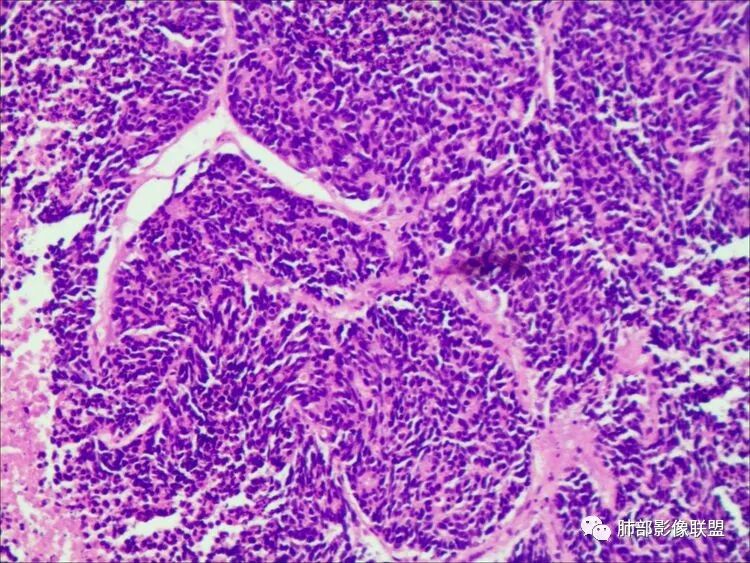

病理结果

大细胞神经内分泌癌

普切:

(右中肺切除标本)神经内分泌癌,细胞较大,有一定量胞浆,核染色质较细,少数细胞可见核仁,倾向大细胞神经内分泌癌,肿瘤大小2cmX2cm×1.6cm,伴有坏死,

未累及脏层胸膜,未见明确脉管內瘤栓及神经侵犯;支气管切缘及肺缝钉切缘均未见癌累及。其余肺组织切片局部见出血性结节伴慢性炎细胞浸润

免疫组化显示瘤细胞:CK7(散在+),CK(pan)(+),CD56(+),Syn(+),CgA(+),TTF-1(+),CD117(+),EGFR(+),p53(3+),p16(+),Ki-67(最高处

约90%+),CD5(-),CK5/6(-),p40(-),p63(-),S-100(-),

Vimentin(-);分子病理结果:EBER(-)。

对于肺神经内分泌癌病理学上有四种分型,即:典型类癌、非典型类癌、小细胞癌(SCLC)及LCNEC。在形态上,LCNEC肿瘤细胞表现为癌细胞体积较大且多形性明显,胞质丰富,泡状核,核仁大,核分裂象易见,核型改变是其主要形态学特征。癌基底细胞呈栅栏状排列,小梁结构,玫瑰样特性。LCNEC同时具有NSCLC和SCLC的病理特点,恶性程度较SCLC相当或略低。免疫组织化学染色法对该肿瘤诊断具有很大作用,因肿瘤细胞能够表达多种神经内分泌标志物,其中以Syn、CgA、CD56为主;  CD56的敏感性最高,但CgA、Syn的特异性更强,这三项中只要有一项为阳性,即可诊断。